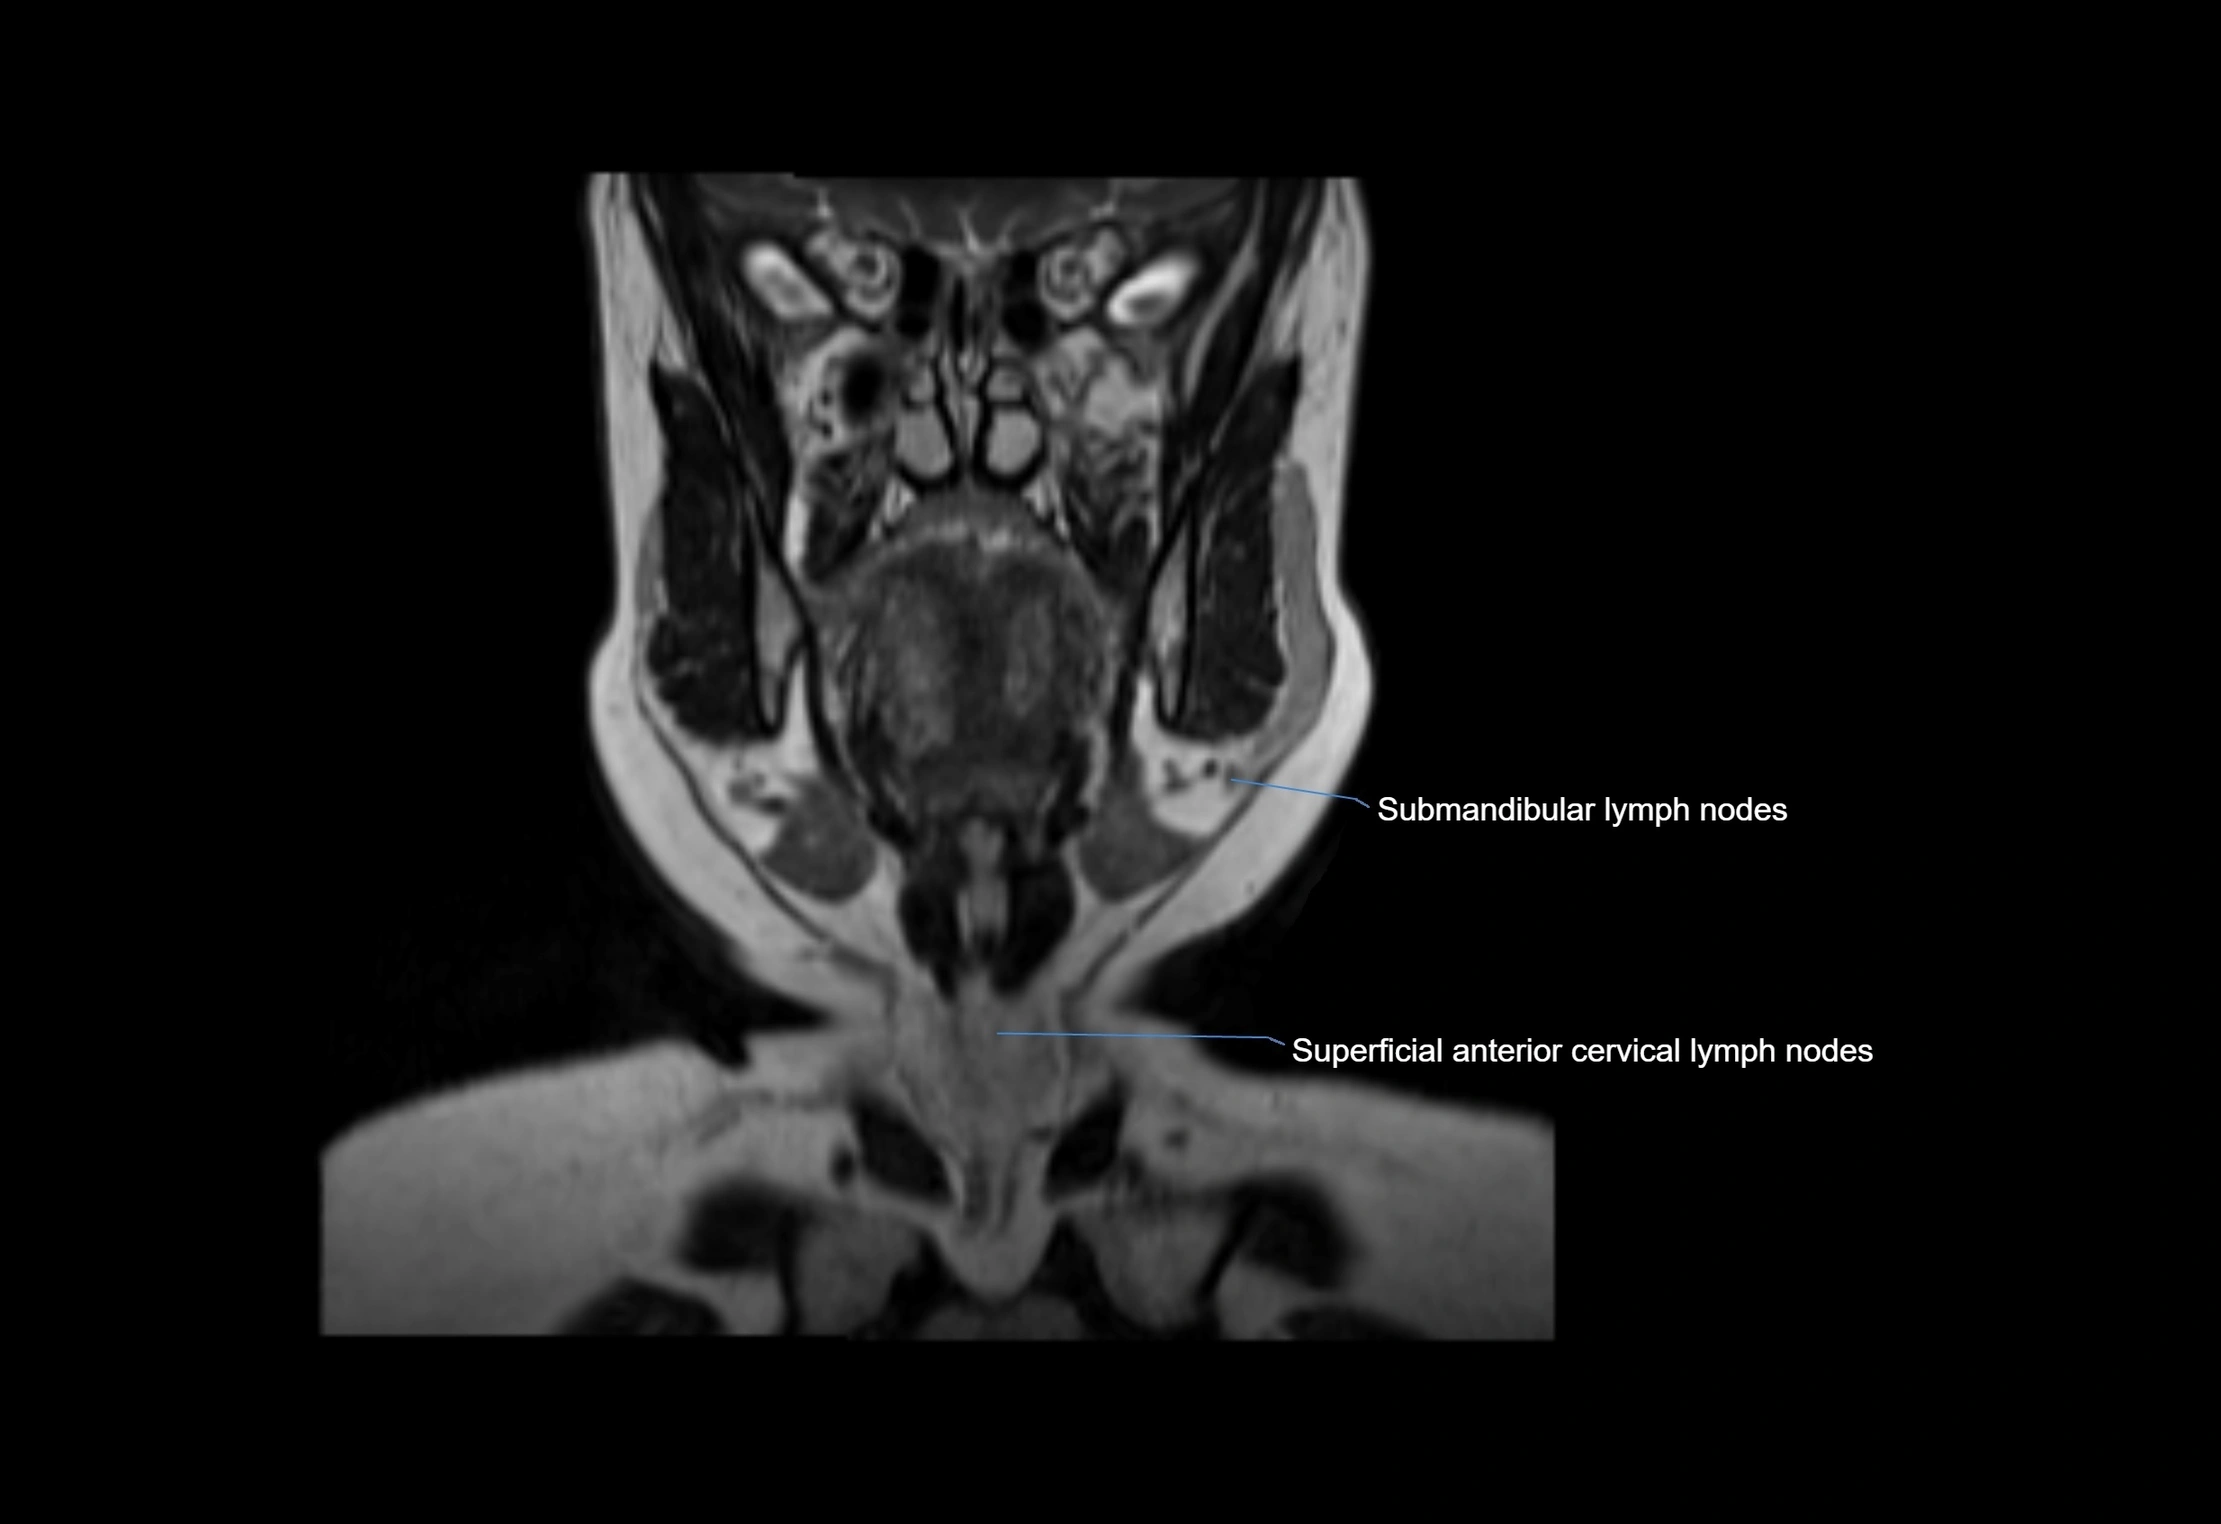

Location

• Found along primary lymph node chains, including preauricular, submandibular, parotid, and occipital regions

• Embedded in subcutaneous fat or superficial fascia, often lateral or posterior to primary nodes

MRI Appearance

T1-weighted images:

• Normal accessory nodes appear as small, oval hypointense to intermediate signal structures within subcutaneous fat

• Surrounded by hyperintense fat, enhancing contrast for visualization

T2-weighted images:

• Nodes show intermediate signal, with surrounding fat bright

• Useful for detecting edema, inflammation, or infiltration

• Fatty hilum may appear slightly hyperintense relative to cortex

MRI images

image